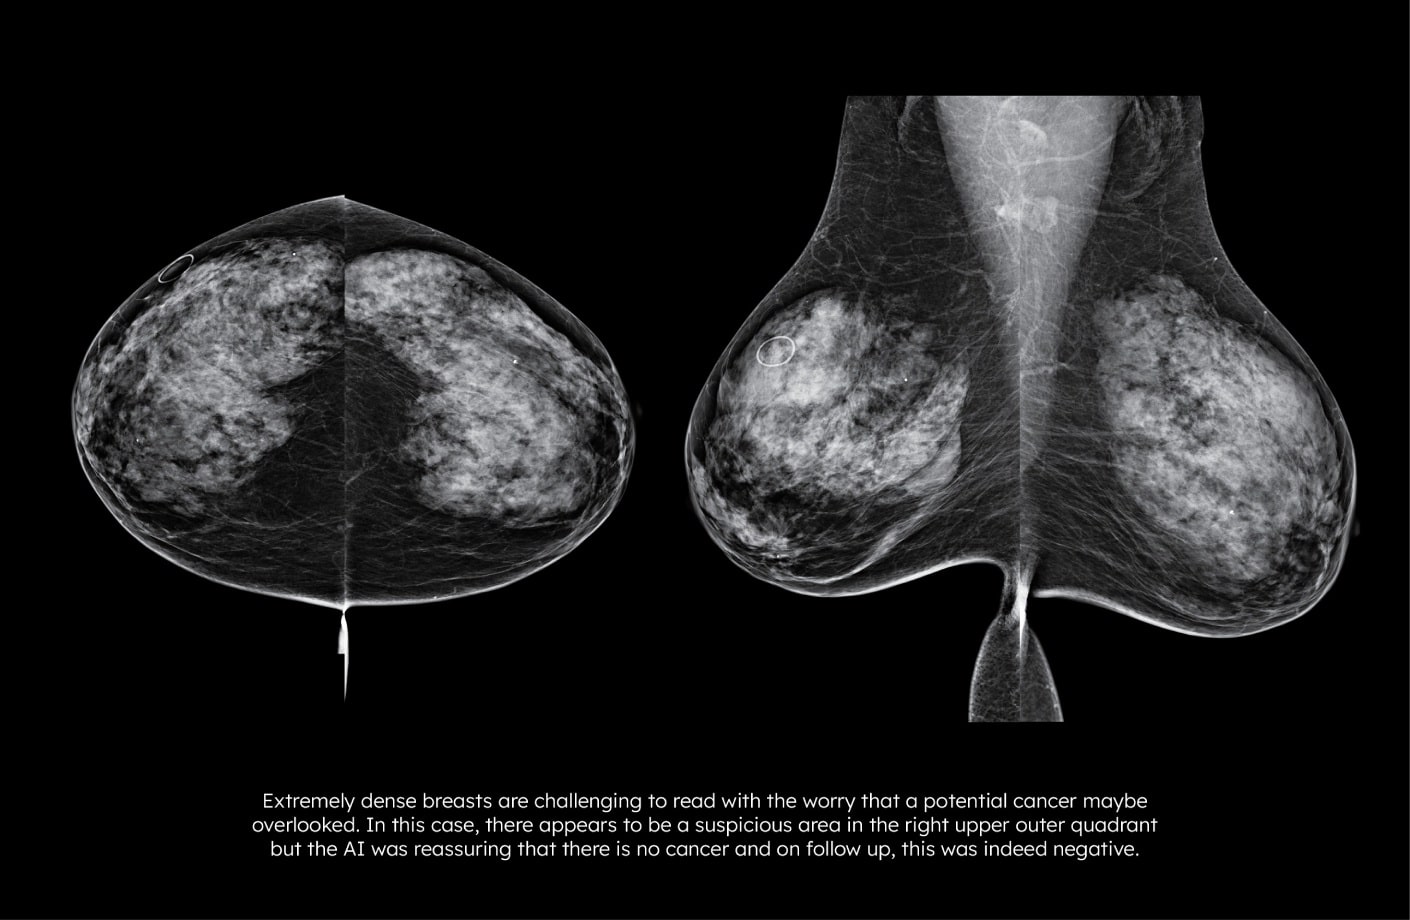

Lunit INSIGHT MMG has an 18% higher accuracy in extremely dense breasts and an 8% higher accuracy in all breast density categories, enhancing detection across tissue types*.

Lunit INSIGHT MMG (2D) mammography software supports earlier breast cancer detection, especially in dense breasts and interval cancers.